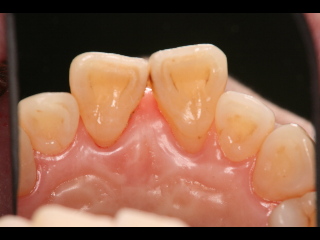

上の前歯の裏側です。右から3番目の歯ぐきが腫れています。

歯もぐらぐらしています。

腫れがなくなり、歯のぐらぐらもなくなりました。